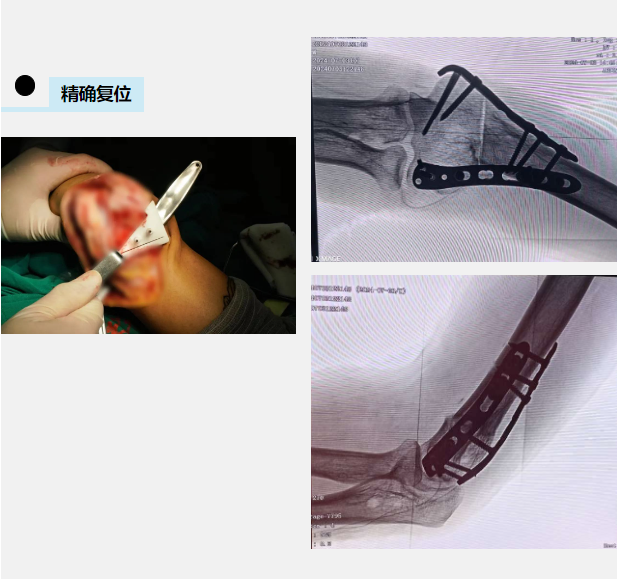

中午12:30,查晔军院长会议一结束就赶来病房了解小磊的情况,询问了他的病史,查看了他大老远带来的之前就诊的影像资料。查晔军院长根据小磊的病情变化详细规划了手术方案。由于手术的特殊性,专门从北京定制了一个“手术利器”——个性化打印截骨导板。此时此刻,困扰小磊20多年的顽疾终于有了解决方案。

5天后,一场河南省首例治疗复杂肘关节疾病的手术在成人ai 高新院区手术室开展:个性化定制3D打印截骨导板辅助肘内翻截骨矫形+外侧副韧带重建,治疗肘关节不稳定。定制的3D打印截骨导板与患者的肱骨外髁完全贴合,大大缩短手术时间,做到精准截骨、精确复位。术中,肱骨截骨钢板内固定后发现胳膊变直了,但是桡骨头仍不稳定,外侧关节囊破损,按术前计划进行了肘关节外侧副韧带重建,恢复肘关节外侧稳定性,防止肘关节活动时桡骨头向外后方脱位。1个半小时,手术顺利结束。